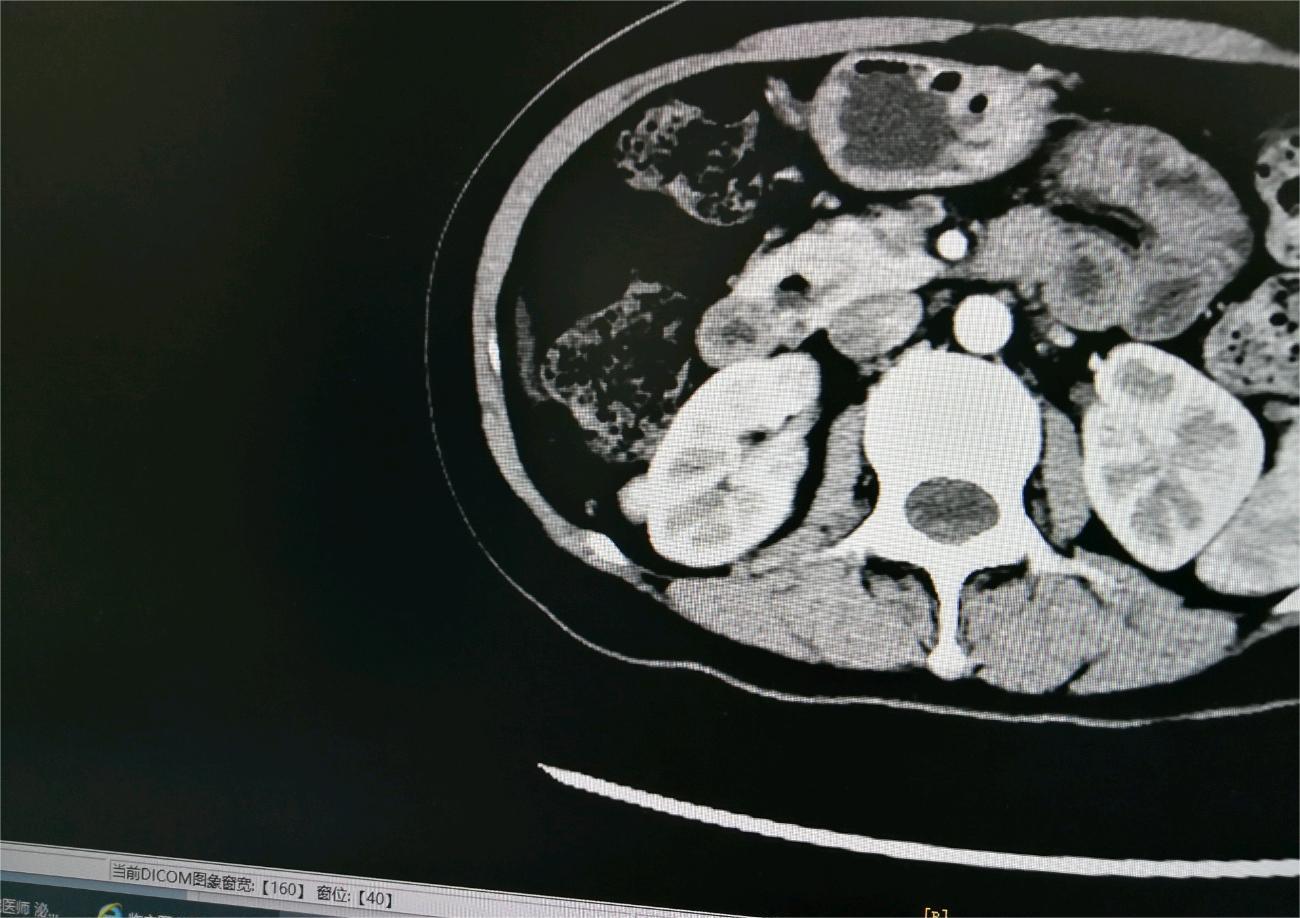

爱你的形状 02024-02-07 患者家属我2岁的女儿通过超声检查发现右肾有个肿瘤,在北京儿童医院做手术,肿瘤术中检测是小圆细胞恶性肿瘤,右肾已摘除,现在术后2天...

花谢花开花满楼 02024-01-30 患者家属 -